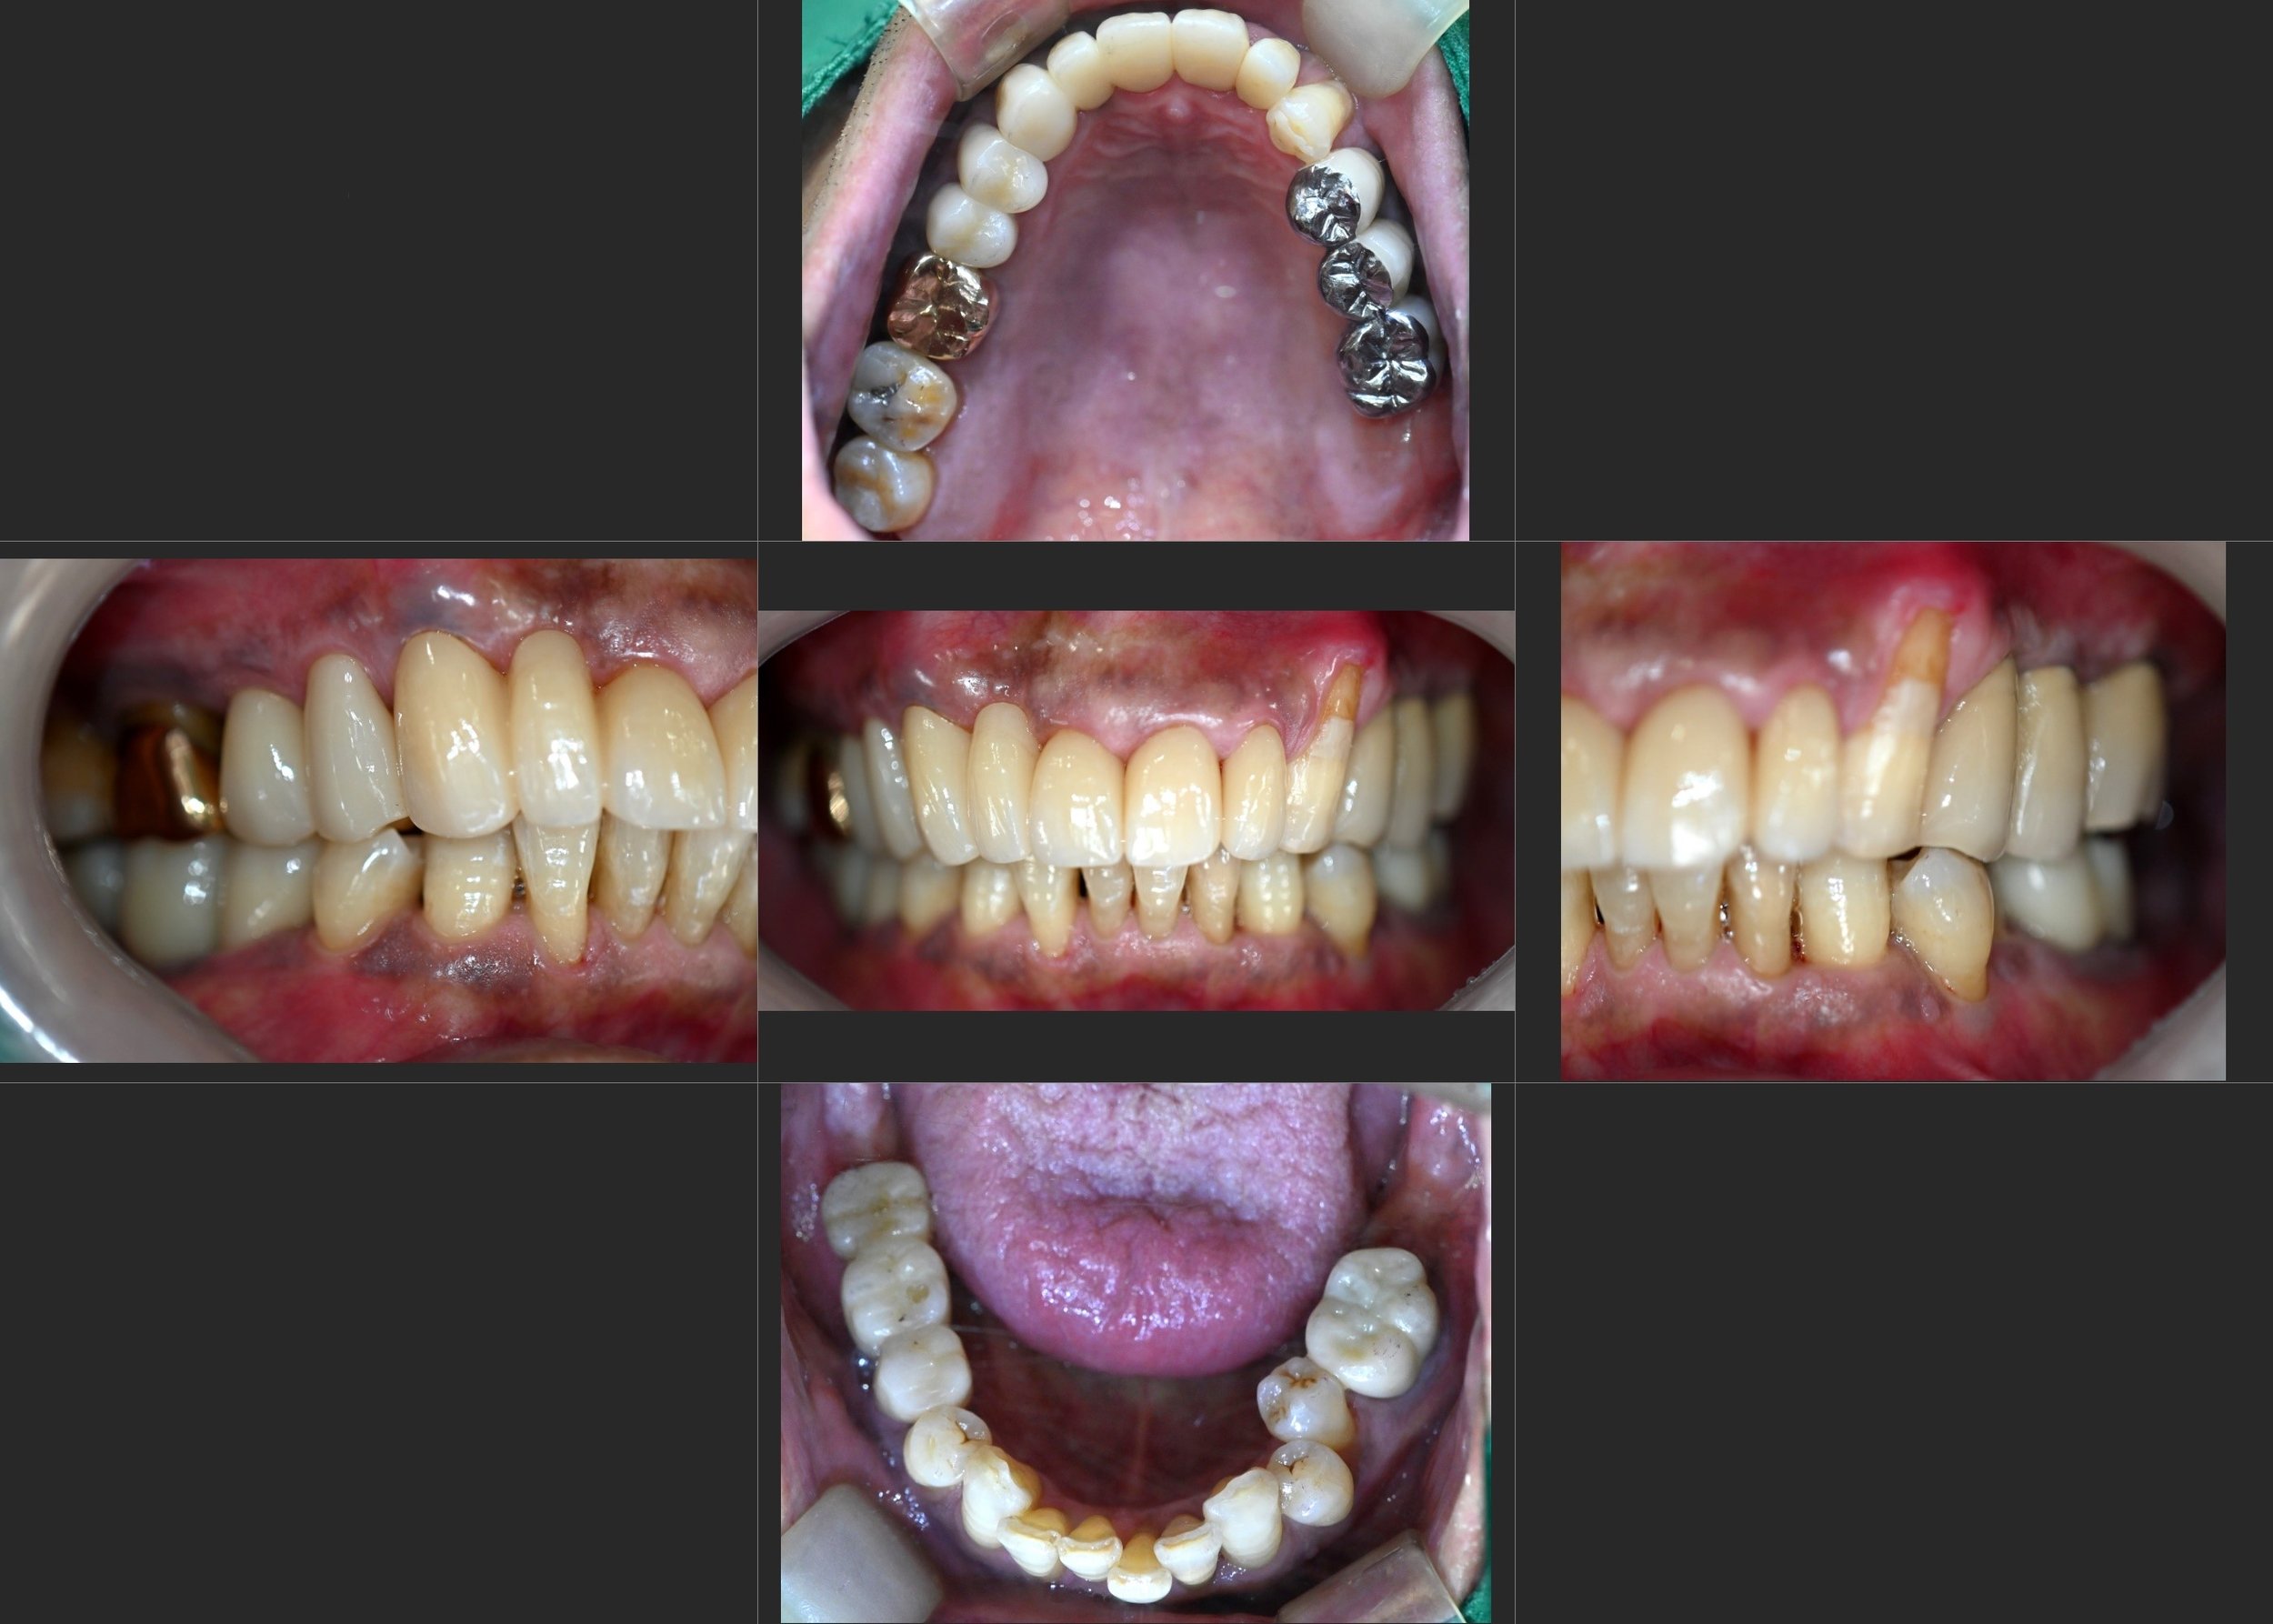

INTRA ORAL - BEFORE